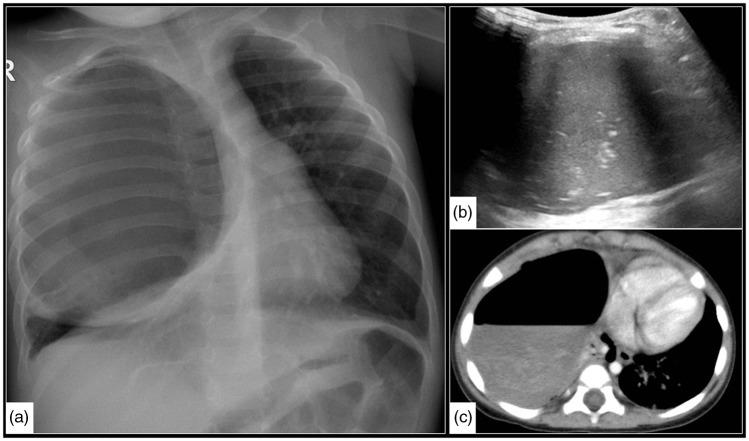

The purpose of this current pictorial review is to define the solitary round pulmonary lesion (SRPL), to familiarize with its prevalence in the pediatric population, and, moreover, to educate radiologists on its vast differential diagnosis and imaging manifestations. Furthermore, by highlighting valuable clues, it intends to assist radiologists efficiently partake in its diagnosis, work-up, and follow-up in order to narrow down the differential diagnosis by working alongside the clinician and combining clinical information, lab results, and radiological findings.

本次影像综述的目的是明确孤立性圆形肺病变(SRPL),使其在儿科人群中的患病率,此外,使放射科医生熟悉其广泛的鉴别诊断和影像学表现。此外,通过强调有价值的线索,旨在帮助放射科医生有效地参与其诊断、检查和随访,以便通过与临床医生合作并结合临床信息、实验室结果和影像学发现来缩小鉴别诊断范围。